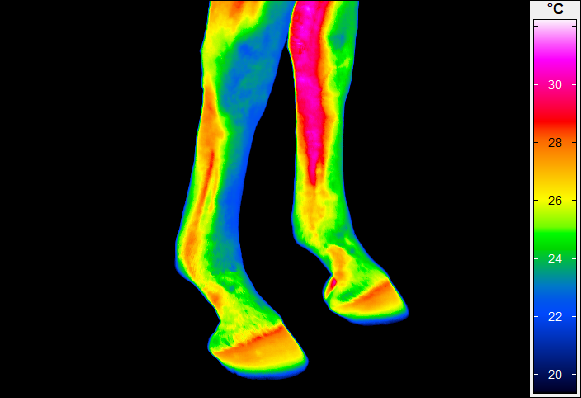

Termografia umożliwia nieinwazyjny pomiar rozkładu temperatury na powierzchni ciała konia. Wynikiem badania jest obraz – termogram, w którym poszczególne barwy odpowiadają określonym zakresom temperatur. Uzyskany rozkład cieplny odzwierciedla przede wszystkim ukrwienie tkanek powierzchownych, aktywność metaboliczną mięśni oraz właściwości izolacyjne skóry i okrywy włosowej.

W warunkach prawidłowych rozkład temperatury ciała konia charakteryzuje się wysokim stopniem symetrii pomiędzy lewą i prawą stroną. Najwyższe wartości temperatur obserwuje się w okolicach dobrze unaczynionych, takich jak oczy, nozdrza czy większe masy mięśniowe, natomiast najchłodniejsze obszary obejmują dalsze odcinki kończyn. Odstępstwa od tego wzorca – zwłaszcza asymetrie przekraczające około 1°C – mogą wskazywać na zaburzenia fizjologiczne lub rozwijające się procesy zapalne.

W medycynie weterynaryjnej i fizjoterapii najszersze zastosowanie termografia znalazła w ocenie dalszych odcinków kończyn, które są szczególnie narażone na urazy w trakcie treningu i użytkowania sportowego.

Metoda ta pozwala na identyfikację obszarów o podwyższonej temperaturze, związanych z zapaleniem ścięgien, więzadeł, torebek stawowych czy okostnej, często jeszcze przed pojawieniem się wyraźnych objawów klinicznych. Oprócz kończyn, istotnym obszarem zastosowania termografii jest grzbiet konia. Zaburzenia w obrębie mięśni przykręgosłupowych, więzadeł nad- i międzykolcowych czy stawu biodrowo-krzyżowego często mają charakter złożony i nie zawsze są łatwe do jednoznacznego rozpoznania przy użyciu standardowych metod. Termografia umożliwia wizualizację zmian w aktywności cieplnej tych struktur, co może wskazywać miejsca przeciążenia, bólu lub kompensacji ruchowych.

W praktyce klinicznej termografia traktowana jest jako narzędzie uzupełniające klasyczne metody obrazowe, takie jak ultrasonografia czy badanie rentgenowskie. Jej największą zaletą jest możliwość wczesnego wykrywania stanów podklinicznych, co pozwala na szybszą reakcję – modyfikację programu treningowego, wdrożenie fizjoterapii lub dalszą, ukierunkowaną diagnostykę.